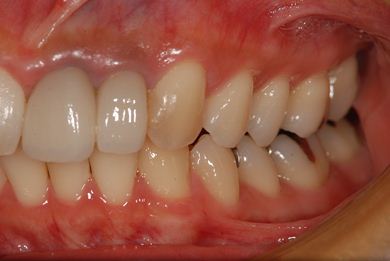

| 性別/年齢 | 女性 / 31歳 | ||||||||||||||||||||||||||||||||

| 主訴 | 前歯の歯茎が黒ずんでいるので、改善したい。 | ||||||||||||||||||||||||||||||||

| 治療方針 | 上顎前歯、メタルボンドセラミッククラウンからオールセラミッククラウンにする事で、審美的回復を行う。 | ||||||||||||||||||||||||||||||||

| 治療内容 | CAD/CAMオールセラミッククラウン2本(セラミック用土台2本) | ||||||||||||||||||||||||||||||||

| 総治療費 | 142,800円 | ||||||||||||||||||||||||||||||||

| 治療期間 | 2ヶ月 |